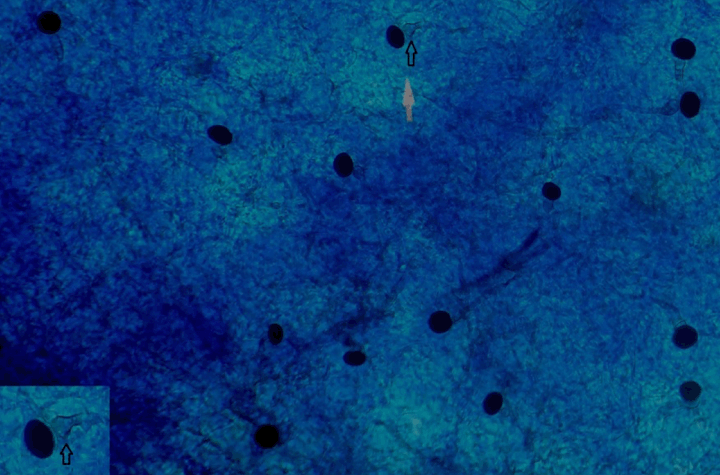

In an attempt to induce sporulation, a banana peel culture was put up, which has been indigenously developed in our lab (Figure 4). Banana peel was cut up into smaller pieces of one square inch and autoclaved in a glass Petri dish. No agar needs to be added since the banana peel itself acts as the source of nutrition. The fungal isolate was inoculated onto the sterile pieces, moistened with a few drops of sterile distilled water and incubated at room temperature. The banana peel simulates the saprophytic environment. Examination with an LPCB mount three weeks later revealed branching septate hyphae, with the conidiophores exhibiting a single conidium at their inflated apex (Figure 5). The conidia were unicellular, very black, ovoid in shape, with the older spores showing a horizontal flattening (Figure 6). The description was found to fit the characteristic "black spores" of Nigrospora sphaerica.

Cursor on image to zoom/Click text to open image

Figure 5: LPCB mount of Nigrospora sphaerica showing septate hyphae and conidiophore with inflated apex and single black conidium (inset) (magnification x400).

The asexual spores (conidia) were found to be typical of the textbook description with conidia ranging from young ovoid to older flattened [8].